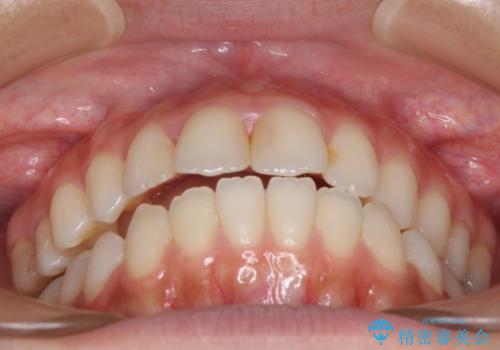

オープンバイトによる見た目を治したい インビザラインでの矯正治療

- オープンバイトのため、話しているときの見た目が気になるとのことで来院された患者様です。

下顎骨は左側にシフトしており、咬み合ったときには奥歯と前歯の一部しか接触していない状態でした。

骨格的な左右差は歯列矯正は改善できないため、上下歯列が全体的に接触することをゴールとしてインビザラインにて矯正治療を行うこととしました。

前歯のデコボコの解消と並行して上下の奥歯を圧下させるようにすることで、前歯を接触させるように計画しました。

上下の隙間に舌が入り込むことがオープンバイトの原因であったため、舌の筋肉のトレーニングも並行して行い、後戻りの抑制を図りました。